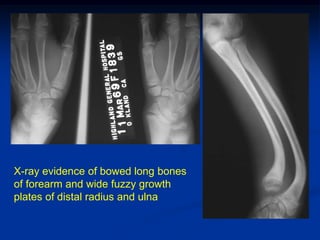

Case #1           Renal Osteodystrophy

13 yr female with past history of glomular tubular nephritis &

now shows deformities of extremities with hyperphosphatemia

X-ray evidence of bowed long bones

of forearm and wide fuzzy growth

plates of distal radius and ulna